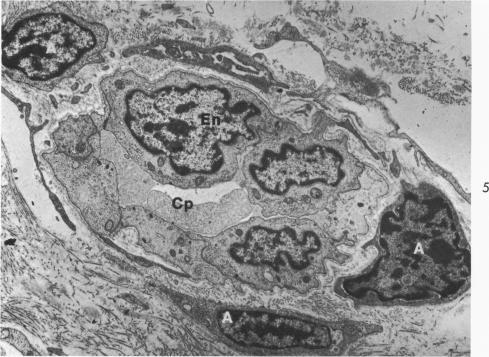

The fine structure alterations in the atrium and atrial appendage, mitral valve and papillary muscle are described in 11 matched patients with chronic rheumatic heart disease. The muscle changes consisted of loss of myofilaments and accumulation of lipid and osmiophilic dense bodies. The connective tissue stroma of the atrium and the mitral valve showed extensive deposition of collagen and elastic fibers. There were numerous foci of collagen degeneration, characterized by fraying of the collagen fibers and accumulation of homogeneous granular material at these sites. Although the muscle changes were more striking, the connective tissue alterations appear important in the evolution of the chronic disease. The extent of collagen degeneration appeared to parallel the degree of collagen formation. The muscle fiber degeneration and connective tissue alterations did not correlate with the clinical findings. At the resolution of the electron microscope, the continuing process in the rheumatic heart appears to be primarily collagen formation and degradation rather than primary degeneration of the muscle fibers. It is the balance of these processes which determine the clinical state of the patient. Acute muscle damage along with evidence of inflammation do not seem to be associated with progressive, chronic rheumatic heart disease.

在11例匹配的慢性风湿性心脏病患者中,描述了心房、心耳、二尖瓣和乳头肌的精细结构改变。肌肉变化包括肌丝丧失以及脂质和嗜锇致密小体的积聚。心房和二尖瓣的结缔组织基质显示出大量胶原纤维和弹性纤维的沉积。有许多胶原纤维变性灶,其特征为胶原纤维磨损以及在这些部位有均匀颗粒物质的积聚。虽然肌肉变化更为显著,但结缔组织改变在慢性疾病的发展过程中似乎也很重要。胶原纤维变性的程度似乎与胶原形成的程度平行。肌纤维变性和结缔组织改变与临床发现无关。在电子显微镜下观察,风湿性心脏病的持续过程似乎主要是胶原形成和降解,而非肌纤维的原发性变性。正是这些过程的平衡决定了患者的临床状态。急性肌肉损伤以及炎症证据似乎与进行性慢性风湿性心脏病无关。